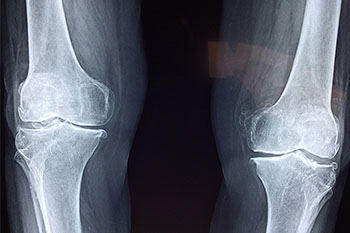

뼈관절염(골관절염, OA)은 퇴행성 관절 연골 파괴 및 만성 관절 질환을 특징으로 하는 골 증식증입니다. 골관절염은 국소화된 질병이며 한방에서는 골마비 및 무릎마비 범주에 속합니다. 골관절염은 관절의 노화를 나타내므로 노인성 관절염이라고 합니다. 넓은 의미의 골관절염에는 다른 무균성 관절염 장애도 포함됩니다.

골관절염의 다른 이름은 관절병증의 병리학적 증상, 즉 연골의 퇴행과 새로운 뼈의 형성에서 비롯됩니다. 이 질병의 발병률은 나이가 들어감에 따라 증가하며 성장한 노인의 관절병입니다.